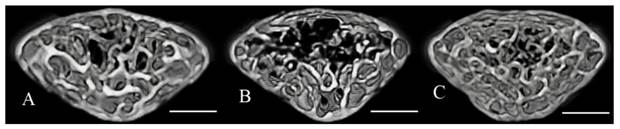

The microstructural parameters of the vertebral trabecular bone are shown in Fig. 2. The trabecular bone volume fraction (BV/TV), trabecular number (Tb.N), and trabecular thickness (Tb.Th) were significantly lower in the stress group compared with the control group. Trabecular separation (Tb.Sp) was significantly higher in the stress group (Fig. 2). BV/TV and Tb.N were significantly higher, and Tb.Sp was significantly lower in the stress/chewing group than in the stress group. Typical 3D reconstructed micro-CT images of the L4 vertebral body are shown in Fig. 3. Images of samples with a BV/TV value closest to the mean BV/TV were reconstructed for each group. The stress group exhibited significant trabecular bone loss compared with the control group. Trabecular volume was higher in the stress/chewing group than in the stress group.

Figure 3

Three-dimensional micro-CT images representative the fourth lumbar vertebral body in the control (A), stress (B), and stress with chewing (C) mice. Images of the sample with the BV/TV that was closest to the mean BV/TV were presented in each group. Scale bar: 0.3 mm.